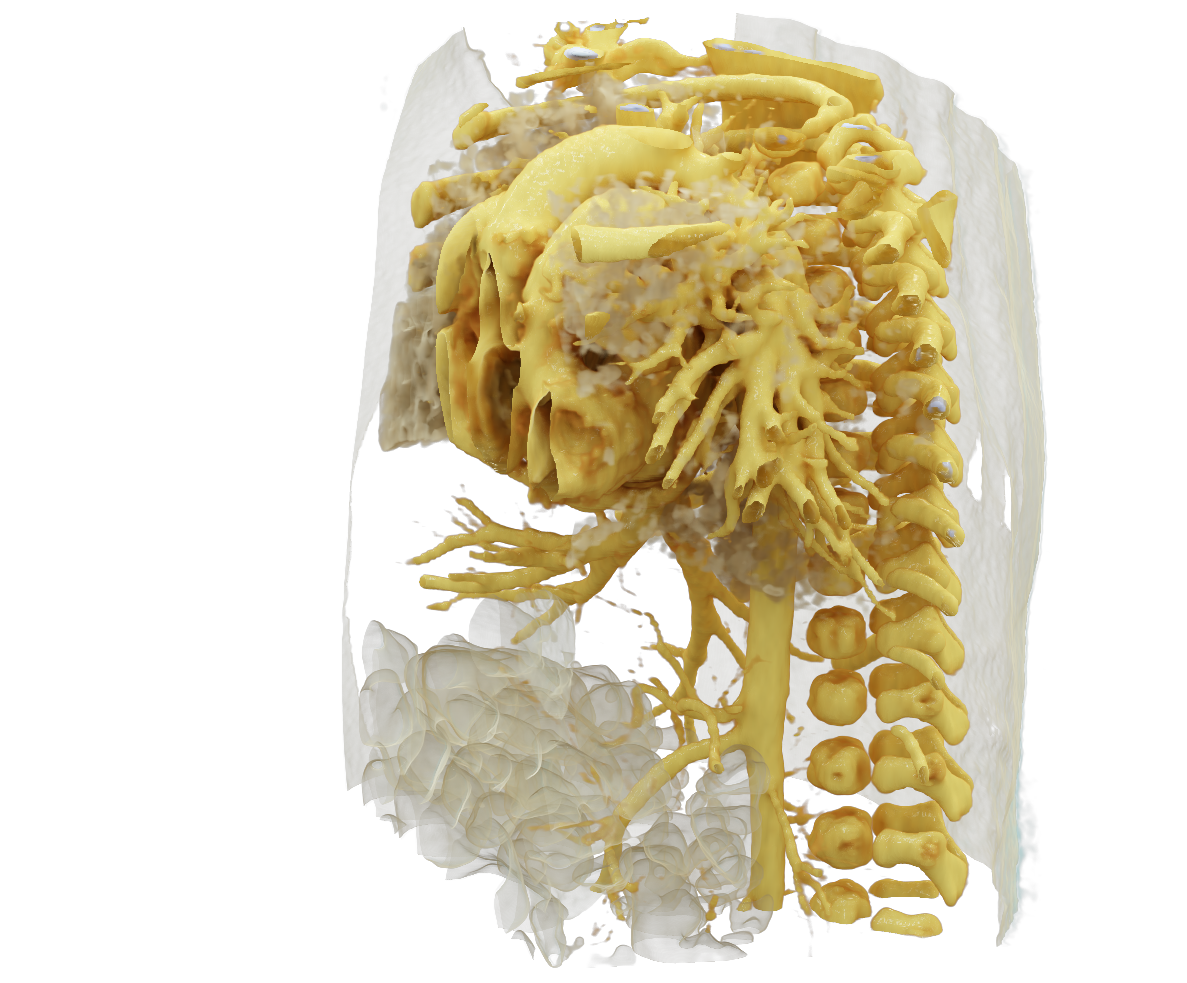

Visualize the smallest structures of the heart realistically without surgery? About the use of a prototype that makes this vision almost tangible.

Cardiac surgery is one of the most difficult procedures, and it gets even more complex when it comes to operating on tiny children’s hearts. Visualization techniques like cinematic rendering provide a detailed 3-D view of the patient’s heart and surrounding anatomy. But what happens when these images are turned into a hologram that can be rotated, zoomed, and looked at from all possible perspectives?